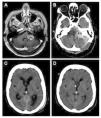

El síndrome pierde sal cerebral (CSW, en sus siglas en inglés) es una complicación rara en la cirugía de los tumores de la fosa posterior. Presentamos a 2 pacientes con tumores del ángulo pontocerebeloso que desarrollaron un CSW posquirúrgico. Ambos pacientes tuvieron un empeoramiento pese a la fluidoterapia y la reposición de sal intensivas. La tomografía computarizada (TC) mostraba una dilatación ventricular leve a moderada que fue tratada mediante un drenaje ventricular externo. Tras la resolución de la hidrocefalia el balance hidroelectrolítico se normalizó rápidamente en ambos pacientes y su situación clínica mejoró. La identificación y el tratamiento precoz de la hidrocefalia obstructiva pueden contribuir al tratamiento del síndrome pierde sal asociado a la cirugía de tumores de la fosa posterior.

Cerebral salt wasting (CSW) is a rare complication in posterior fossa tumour surgery. We present two patients with cerebellopontine angle (CPA) tumours who developed cerebral salt wasting postoperatively. Both patients deteriorated in spite of intensive fluid and salt replacement. On CT scan the patients presented mild to moderate ventricular dilation, which was treated with an external ventricular drainage. After the resolution of hydrocephalus, fluid balance rapidly returned to normal in both patients and the clinical status improved. Identification and treatment of secondary obstructive hydrocephalus may contribute to the management of CSW associated to posterior fossa tumour surgery.